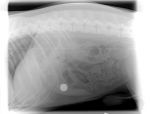

We know what you mean as we had Cody into the vets at the beginning of June with a stomach ache.

Xrays showed that he had swallowed a nice sized round fishing sinker (about 50 grams in weight).

Codys sinker (Medium).jpg